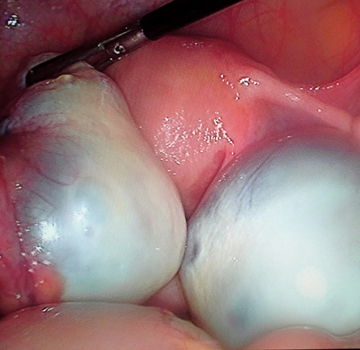

Quiste de ovario

Consiste en un crecimiento de líquido dentro o en la superficie exterior de uno de los ovarios, siendo un padecimiento que afecta a muchas mujeres. La mayoría de estos crecimientos son inofensivos, causan solo incomodidad menor o ningún síntoma en absoluto, y desaparecen sin tratamiento en unos meses. Sin embargo, algunos quistes pueden causar síntomas severos y requieren tratamiento urgente.

Síntomas: Dolor pélvico, dolor agudo o sordo en el área baja abdominal de un lado del cuerpo donde se ubica el quiste, incomodidad abdominal: sensación de pesadez o sensación de plenitud en el abdomen. sensación de hinchazón.